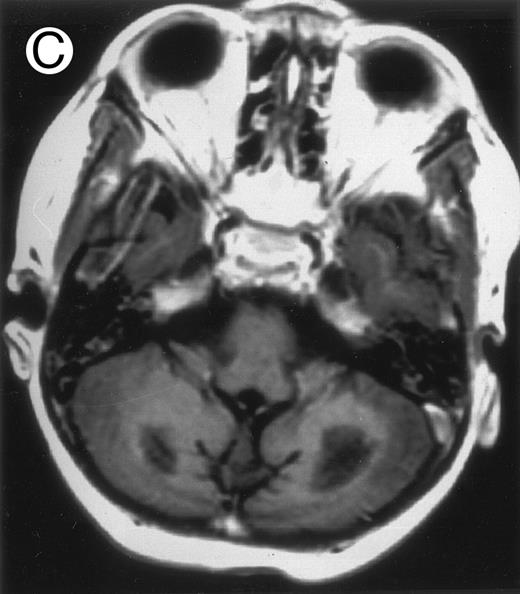

Three different aspects of brain imaging in HLH patients. (A) CT scan of a 3-month-old baby showing a large subdural effusion, several necrotic areas and hypodensities of the white matter. (B) Brain magnetic resonance of a 14-month-old boy showing large confluent areas of hypersignal in T2-weighted images. (C) Large symmetrical necrotic areas of cerebellar white matter in a 41/2-year-old girl (MRI).

Among the nine children with initial neurological symptoms, seizures were the most frequent initial symptom in the youngest patients, whereas ataxia was found in the two oldest patients (46 and 58 months old, respectively) (Table 1). All nine patients had the same CSF abnormalities as patients with meningitis only. Eight of these nine patients had a neuroradiological study performed at the time of their first neurological symptoms (Table 1). The two most frequent lesions were focal necrosis with parenchymal volume loss and atrophy (Fig 2A and C) and white matter abnormalities (Fig 2B). Several small focal lesions with hypersignal at MR imaging that enhanced after administration of gadopentate dimeglumine (or contrast on CT scan) were also observed in two cases.

Together, 19 patients had primary severe CNS disease progression or CNS relapse (Fig 1). Three of 19 had a CNS relapse characterized by meningitis only. Neurological symptoms occurred in 16 of these 19 patients (9 from the onset and 7 after the initial meningitis) (Fig 1). No clinical or neuroradiological difference was detected between the patients who developed neurological symptoms as the initial CNS manifestation or after initial meningitis (Table 1). The occurrence of these neurological manifestations marked a turning point in the evolution of the disease, as chemotherapy led to an improvement of the neurological symptoms in only three patients despite the use of intensive treatment by MTX IT. In these three patients, neurological sequelae persisted after the first symptoms and a relapse occurred within 3 to 10 months. Brain imaging was repeated during chemotherapy for four patients with progression of the CNS disease: in three patients, a severe brain atrophy developed (Fig 3A and B) and in the last patient who initially had contrast enhancement in cerebellar white matter, a cerebellum parenchymal loss was observed (Fig 2C). All of these 19 patients treated by chemotherapy only (n = 15) died during a last episode of coma and brain stem symptoms associated with a systemic hemophagocytic syndrome, 6 ± 6 months after the first neurological symptom (irrespective of the age at this first event). Four of these 19 patients were transplanted (one patient received an HLA-identical BMT, three an HLA-partially identical BMT). Median delay between diagnosis and BMT was 14 months (range, 2 to 20 months). All of these four patients died of BMT-related toxicity and/or disease progression.

Abnormalities on brain imaging appeared to roughly parallel the severity of clinical manifestations. All patients with neurological symptoms, but also half of the patients with initial meningitis, had abnormal brain imaging usually consisting of a combination of diffuse white matter abnormalities and necrotic areas with parenchymal volume loss, as previously described.8,23 In patients with isolated meningitis, however, only white matter abnormalities were detected, whereas necrotic lesions and cerebral atrophy were found in patients with neurological symptoms. These lesions progressed despite chemotherapy. Previous neuropathological studies have demonstrated infiltration by monocytes and activated lymphocytes of leptomeninges and brain parenchyma along penetrating vessels.24,25 Infiltration is associated with focal and confluent areas of myelin pallor, as well as neuronal loss, tissue necrosis, and cavitation,24,25 findings that were also demonstrated in the neuropathologic study of five patients in our series. Leukocytes infiltrating the CNS probably secrete cytokines and other neurotoxic factors, such as tumor necrosis factor-α (TNF-α), which may be responsible for the myelinic alteration observed in neurologically asymptomatic patients. Infiltrating leukocytes could also activate in parallel the numerous resident brain macrophages (the microglial cells) and astrocytes, which in turn, can secrete neurotoxic glutamate and free radicals.26